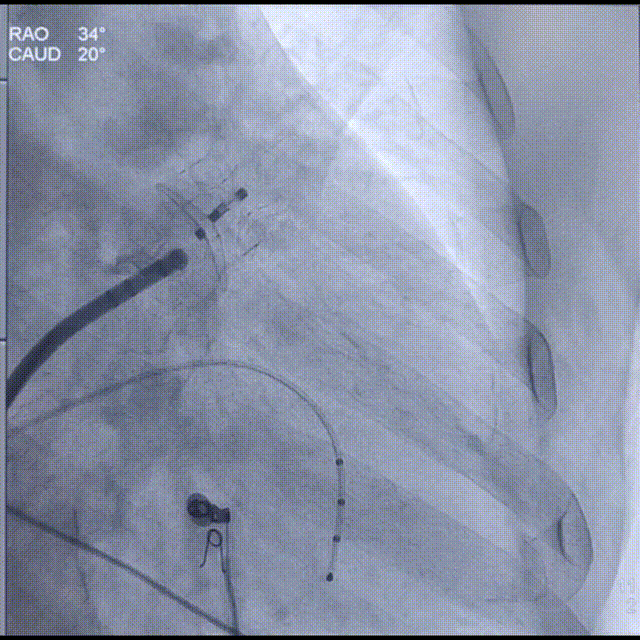

通过LAA造影和工作体位测量,结果显示患者左心耳开口直径为25mm,着陆区直径为20mm,深度为32mm;根据数据,手术团队决定选择Laager®封堵器2429型号进行后续操作;

工作体位造影

画线测量

按照Laager®封堵器常规“退-推-退-推”释放方式,依次展开固定盘及封堵盘。造影见固定盘展开在预设位置,封堵LAA内侧;封堵盘上缘位于嵴内,封堵良好无明显残余分流;

Laager®封堵器2429型号固定盘展开后造影

Laager®封堵器2429型号封堵盘展开后造影

随后,进行牵拉试验时发现封堵器可拉出心耳,未锚定成功。因此决定增大封堵器型号,换用Laager®封堵器2631型号;

Laager®封堵器2631型号封堵盘展开过程

Laager®封堵器2631型号固定盘展开后造影

换用Laager®封堵器2631型号后造影提示位置良好,多体位下造影见封堵良好,封堵盘上缘在心耳口内,无残余分流;

封堵盘展开后,工作体位造影

封堵盘展开后,头位造影

再次进行牵拉试验未见固定盘位移,锚定良好。满足Laager®封堵器“STEP”释放原则,遂解脱钢缆释放封堵器。释放后再次造影,封堵良好,无残余分流。

释放后工作体位造影